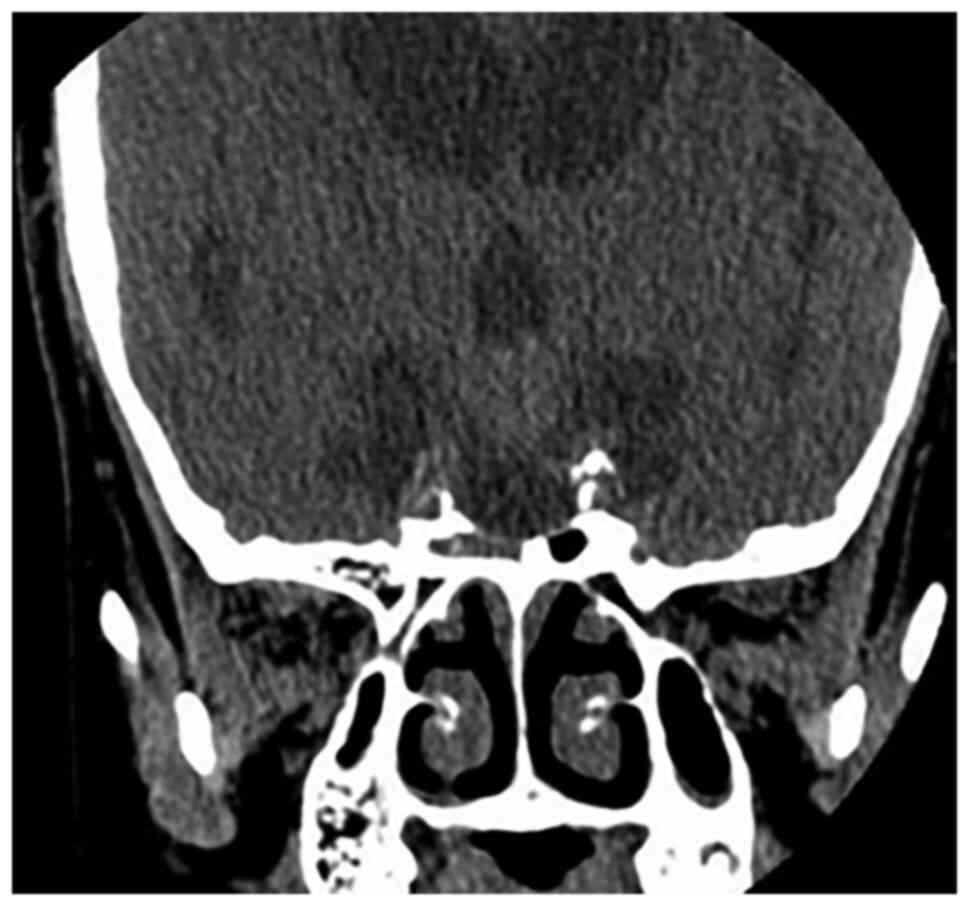

Craniopharyngioma resection and aneurysm clipping performed simultaneously by pure endoscopic endonasal approach: A case report and literature review

Craniopharyngioma is one of the most challenging issues for neurosurgeons as a brain tumor. Among the approaches of neurosurgery, in comparison to craniotomy, the endoscopic endonasal approach (EEA) has risen in popularity over the last two decades; unruptured intracranial aneurysms are relatively commonly found in the general population. The EEA as a new paradigm in the treatment of aneurysm has been reported to successfully clip dozens of cases of intracranial aneurysm. However, when reviewing the domestic and foreign literature, it appeared that cases of craniopharyngioma complicated with intracranial aneurysm purely treated by EEA have not been reported so far. In the present study, the published literature regarding endoscopic endonasal surgery for craniopharyngioma and intracranial aneurysms was reviewed, accompanied with a case of craniopharyngioma complicated with intracranial aneurysm, both of which were simultaneously treated by EEA.